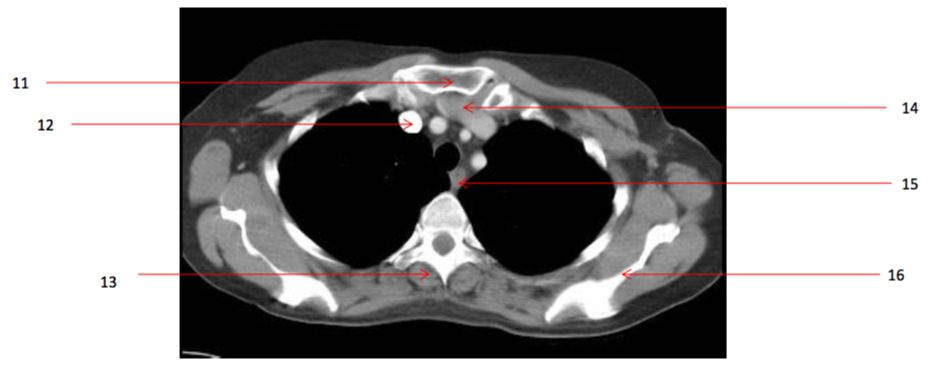

27

Number 34?

Rt ventricle

28

Number 31?

Ascending aorta/aortic valve

31

Number 25?

Spinal injury

33

Number 48?

Aortic valve

34

Number 26?

Rt atrium

35

Number 32?

Left Atrium

36

Number 30?

37

Number 42?

Lt ventricle

38

Number 41?

Descending thoracic aorta

39

Number 38?

40

Number 45?

Intraventricular septum

41

Number 40?

Lt atrium

42

Number 49?

44

Number 37?

decending thoracic aorta

45

Number 35?

46

Number 46?

pulmonary trunk

47

Number 39?

48

Number 43?

Oesophagus

49

Number 47?

Ascending aorta